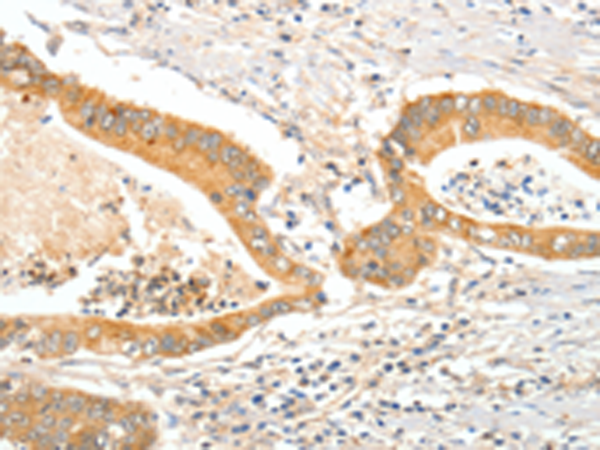

分类: 科研抗体货号: P10703别名: ARO; ARO1; CPV1; CYAR; CYP19; CYPXIX; P-450AROM应用: IHC反应种属: Human, Mouse, Rat